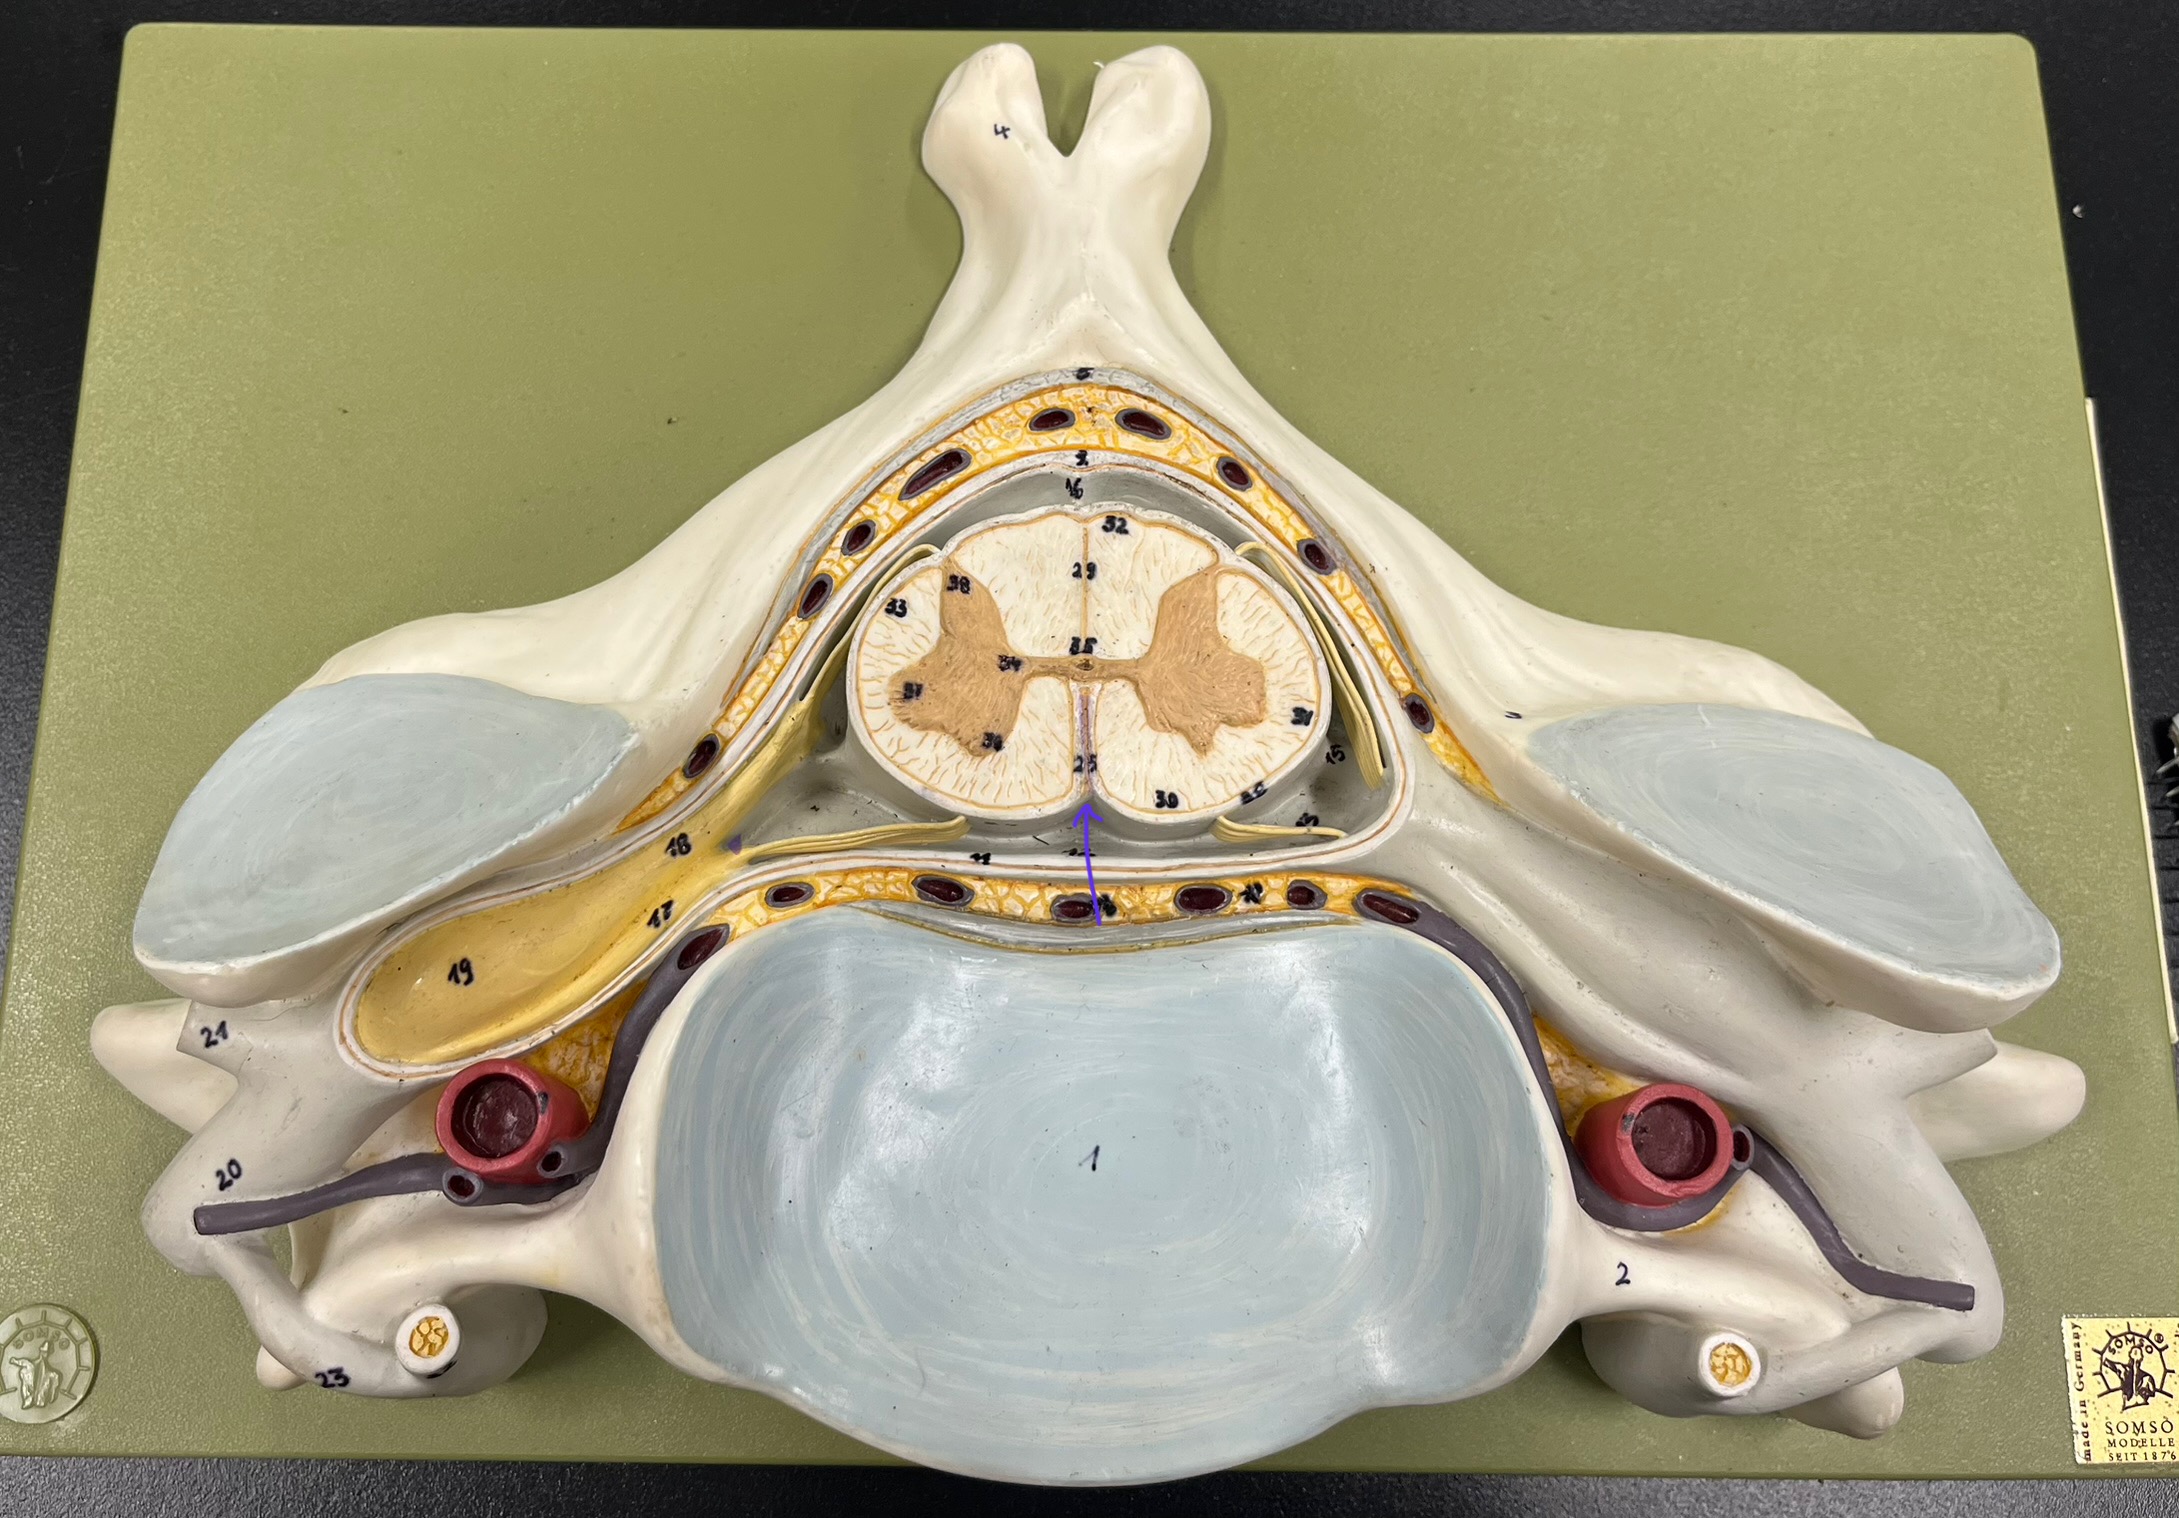

epidural space

dura mater

subdural space

arachnoid mater

subarachnoid space

pia mater

denticulate ligaments

What is the groove here?

anterior median fissure

posterior median sulcus

posterior (dorsal) horn

posterior (dorsal) horn; R—>L

anterior (ventral) horn

lateral horn (selected models)

gray commissure

central canal

anterior column

lateral column

posterior column

white commissure

posterior (dorsal) root ganglion

What is the bulb here?

posterior (dorsal) root ganglion

posterior (dorsal) root

posterior (dorsal) root

anterior (ventral) root

anterior (ventral) root

dorsal ramus

dorsal ramus

ventral ramus

ventral ramus

rami communicantes

rami communicantes

sympathetic chain ganglia

sympathetic chain ganglia